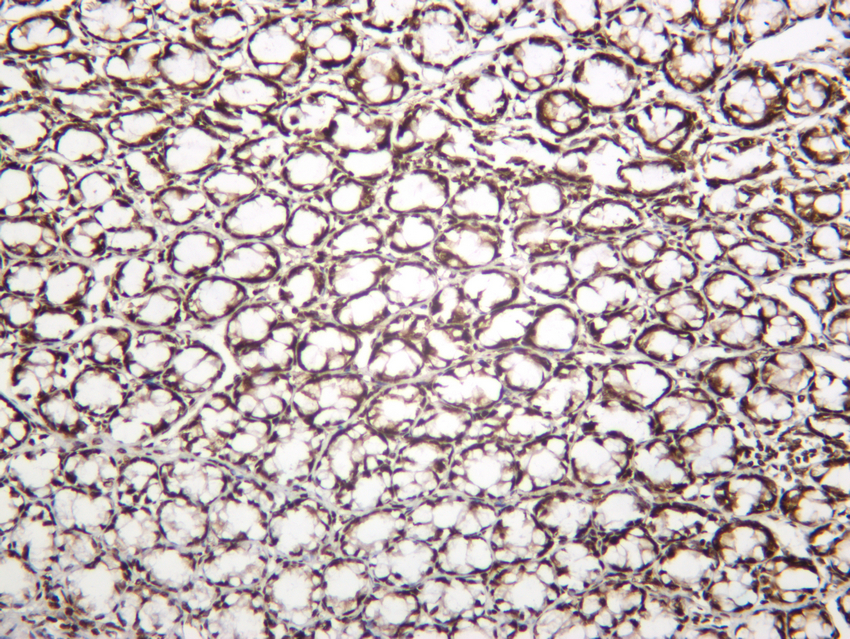

Histone H2A.X(Phospho-Ser139) Rabbit mAb#13343

- IHCImmunohistochemistry